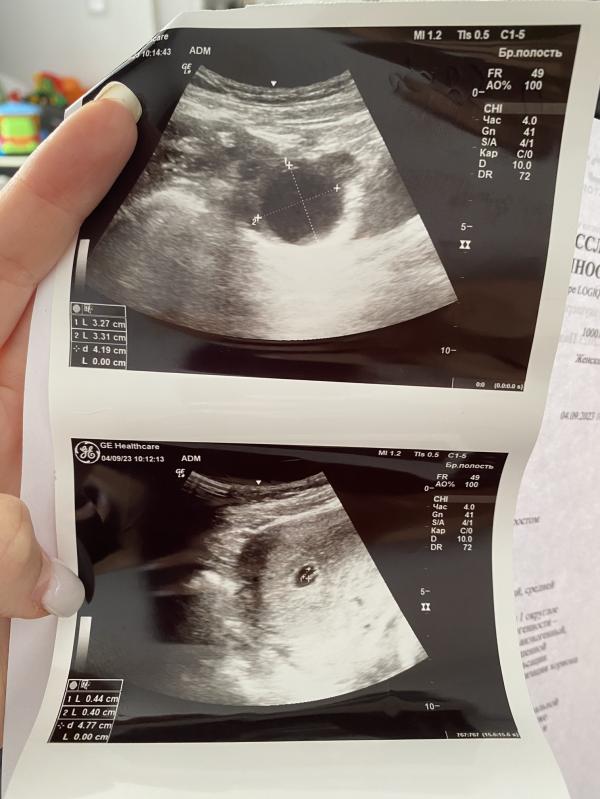

Не удержалась, сгоняла сегодня на первое узи, хотя хотела раньше 8 недель не делать!

Итак,

Срок 6,3

КТР 4мм

Желточный мешочек 4,4мм

Плодное яйцо 11,5мм

Сердцебиение в виде пульсации!!!

Эмбрион соответствует 6-6,5 неделям!

Кстати, узи смотрели через живот-трансабдоминально!